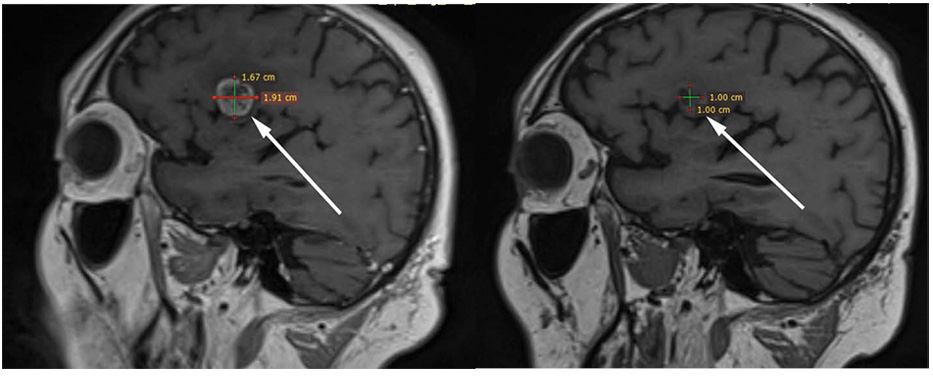

В декабре 2021 г. – лучевая терапия на весь объем головного мозга, суммарная очаговая доза 30 Гр, при контрольной магнитно-резонансной томографии (МРТ) головного мозга с внутривенным контрастом – появление новых очагов в головном мозге (суммарно до 11). С февраля по апрель 2022 г. проведено 3 курса терапии препаратом трастузумабом дерукстеканом, в динамике – частичный интракраниальный ответ (рис. 6, 7).

Рис. 7. Пациент №11, сагиттальная проекция, сравнение МРТ головного мозга с КУ от февраля 2022 г. (слева) и от апреля 2022 г. (справа), уменьшение целевого очага в левой теменной доле.

Fig. 7. Patient No.11, sagittal plane, comparison of contrast-enhanced brain MRI dated February 2022 (left) and April 2022 (right), reduction of the target lesion in the left parietal lobe.